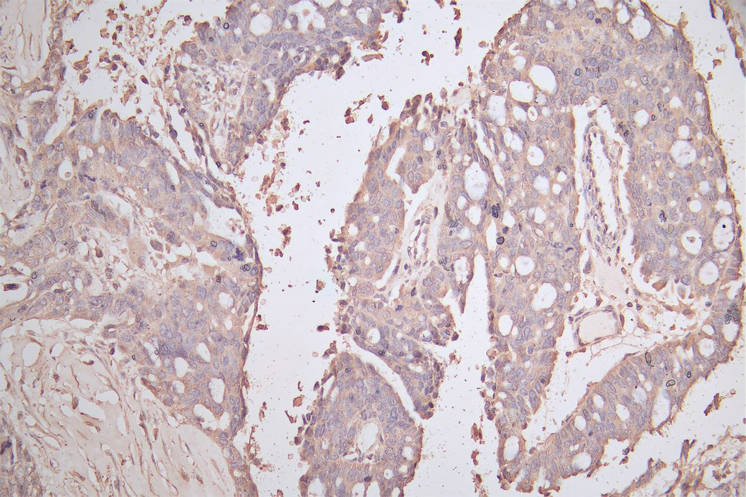

IHC image of CSB-RA005034MA1HU diluted at 1:200 and staining in paraffin-embedded human endometrial cancer performed on a Leica BondTM system. After dewaxing and hydration, antigen retrieval was mediated by high pressure in a citrate buffer (pH 6.0). Section was blocked with 10% normal goat serum 30min at RT. Then primary antibody (1% BSA) was incubated at 4°C overnight. The primary is detected by a Goat anti-Mouse IgG labeled by HRP and visualized using 0.05% DAB.